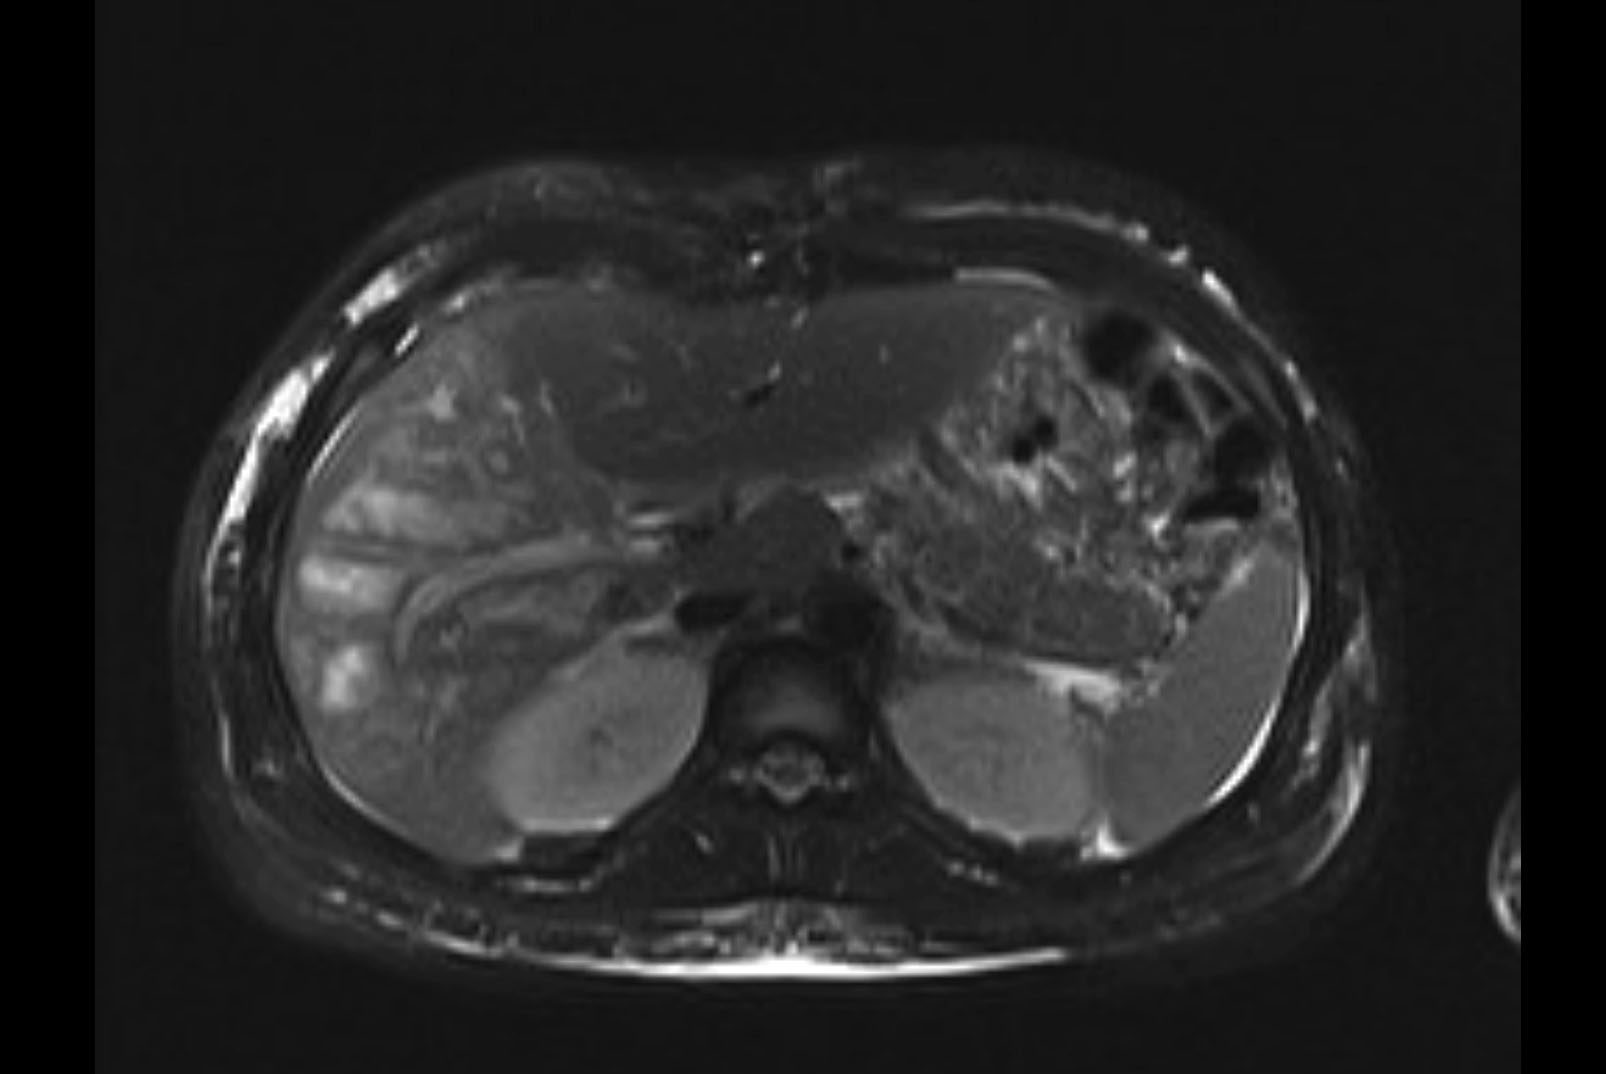

Imaging Analysis

Look through the patient's CT scan to identify any areas of concern for the necessary procedure.

MRI T2

Based on initial findings, which issue(s) would you be most concerned about?